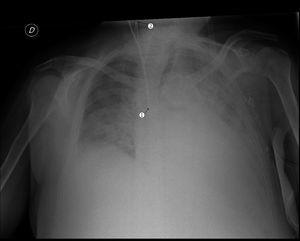

La enferma ingresó por sepsis secundaria a infección del catéter yugular, por lo que se decidió la retirada del mismo y la canalización, primero de catéter femoral, y posteriormente de nuevo catéter yugular derecho (Mahurkar, 3,8 mm x 16 cm), localizando la vena yugular interna derecha por la vía anterior, sin control ecográfico. Se localizó correctamente dicha vena, y se introdujo la guía metálica, sin resistencia en la maniobra. La introducción del dilatador, previa a la implantación del catéter, no fue posible por la intensa fibrosis del tejido celular subcutáneo secundaria a los múltiples catéteres previos a ese nivel. Se procedió a retirar la guía metálica, pero sólo pudieron extraerse 5 cm, con enorme dificultad, permaneciendo el resto en la luz vascular. Una radiografía de tórax en decúbito mostró el acodamiento de la guía en la luz venosa, secundario a una probable estenosis en la vena yugular interna (figura 1). La paciente fue evaluada por el servicio de radiología vascular, que descartó la extracción de la guía mediante radioscopia ante el elevado riesgo de la maniobra. El servicio de virugía vascular, bajo anestesia local, realizó una incisión cervical profunda y, mediante manipulaciones y tracciones repetidas, extrajo la guía (figura 2). Tras el procedimiento la paciente permaneció estable hemodinámicamente, con anemización secundaria, que requirió transfusión sanguínea.

Figura 1. Acodamiento de guía metálica secundaria a probable estenosis en vena yugular interna. Ascenso de la guía hasta alcanzar la región cervical de la vena yugular interna.